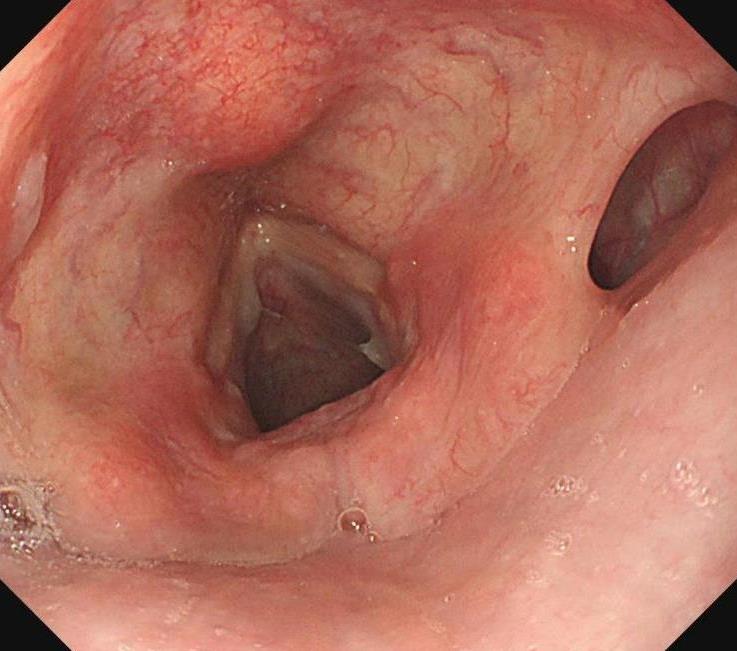

摘要:目的 探究一次性eyeMax洞察胰胆管成像系统辅助内镜逆行阑尾炎治疗术(ERAT)治疗阑尾炎的效果及安全性。方法 回顾性分析2023年4月-2024年9月在该院就诊,通过影像学或内镜检查确诊的54例非复杂性阑尾炎患者的临床资料。所有患者均行eyeMax洞察胆胰管成像系统辅助ERAT,于直视下观察阑尾腔,并通过冲洗、取石、扩张狭窄和支架引流等措施治疗阑尾炎。观察手术相关指标、术后疼痛程度、并发症发生情况、术后1年内复发率、结肠镜下表现、胰胆管成像系统下表现和胆胰管成像系统下治疗情况。结果 54例患者均顺利完成手术,技术成功率为100.0%,手术时间(60.6±27.9)min,住院时间(3.6±1.5)d;30例(55.6%)阑尾开口及周边黏膜充血水肿,2例(3.7%)可见脓液及污秽物流出;54例(100.0%)患者阑尾腔内壁充血水肿,51例(94.4%)可见腔内絮状物、脓液或脓苔附着,25例(46.3%)可见腔内粪石,15例(27.8%)可见管腔走形迂曲或狭窄。所有患者予以eyeMax洞察胰胆管成像系统治疗,简单灌洗54例,网篮取石20例,支架引流25例。术后VAS评分为0(0,0)分,明显低于术前的6(3,7)分,手术前后比较,差异有统计学意义(Z = -6.24,P = 0.000)。所有患者术后症状均暂时缓解,术中及术后未发生穿孔和大出血等严重不良事件。随访1年内,阑尾炎复发率为20.4%(11/54)。结论 EyeMax洞察胆胰管成像系统辅助ERAT是治疗非复杂性阑尾炎安全和有效的疗法,其具有直视下精准操作、保留阑尾功能、症状快速缓解、无X线暴露和精准诊疗阑尾病变等优势。值得应用于临床。